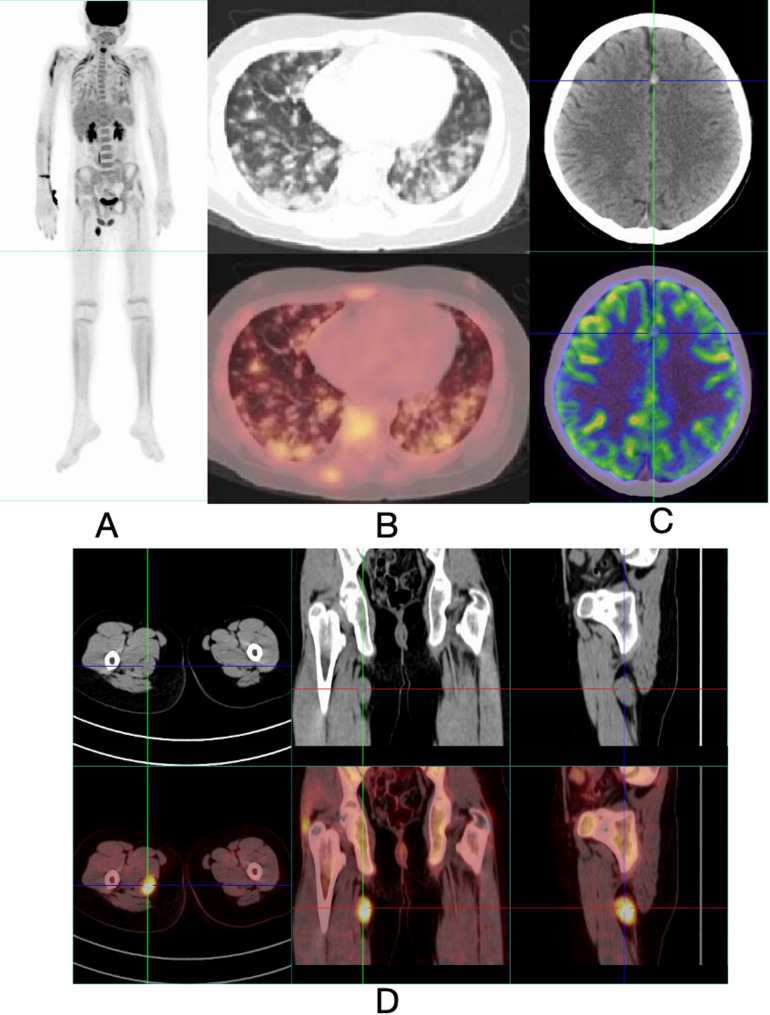

Methods: We report a rare case of ES in a pediatric patient presenting with DAH and intracranial hemorrhagic lesions. Diagnostic evaluations included high-resolution chest CT (HRCT), bronchoscopy, brain MRI, lung biopsy, Positron emission tomography - computed tomography (PET-CT), and biopsy of a mass in the right thigh. Fluorescence in situ hybridization was performed to detect SMARCB1 (INI1) gene deletion.

Results: A 13-year-old male presented with anemia and later developed hemoptysis with a decreased hemoglobin level. HRCT revealed bilateral ground-glass opacities consistent with DAH. Extensive autoimmune and infectious workups were all negative. Brain MRI demonstrated microhemorrhages. Despite corticosteroid therapy, the patient's condition worsened. PET-CT identified a hypermetabolic soft tissue mass in the right thigh, which on histopathological examination was confirmed as INI1-deficient ES. FISH analysis confirmed INI1 deletion.